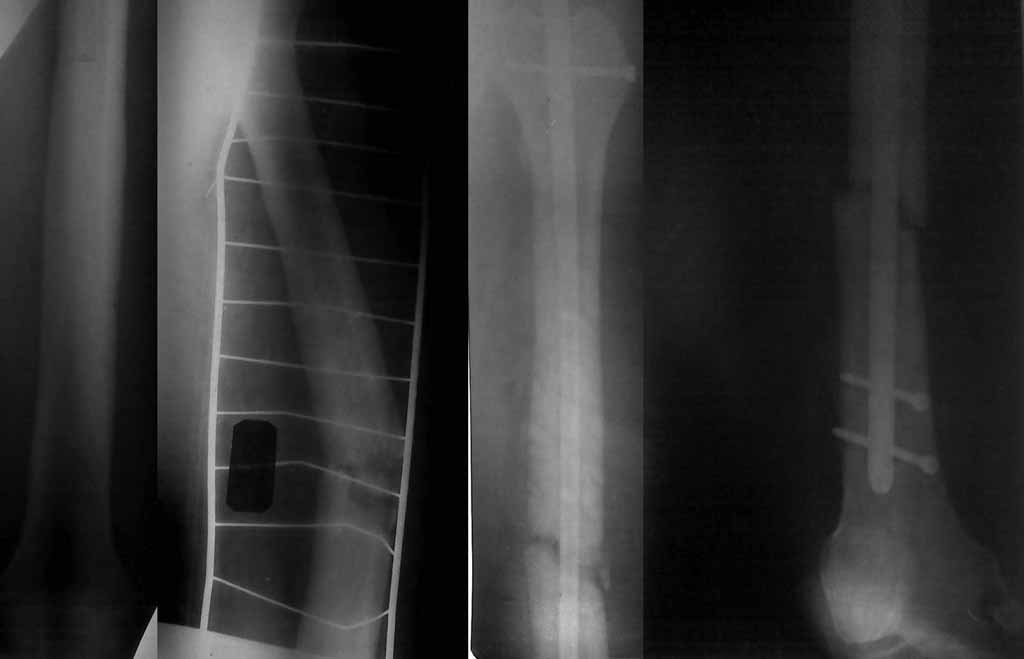

[Ortho] Патологический перелом бедра

Здравствуйте, коллеги. Досылаю рентгенограммы, качество низкое, извините.